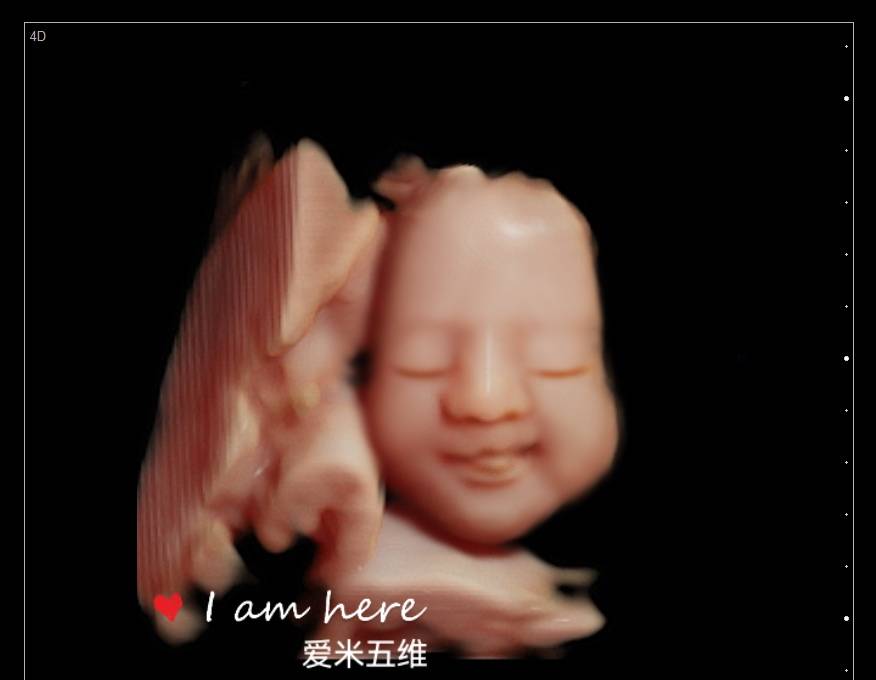

第一次五维看到了宝宝,好可爱,看的非常清楚,打印出来的照片也很清晰,第一次看到宝宝在肚子里的样子真的很激动,服务特别亲切,拍个五维还是很值得的

爱米孕婴摄影有着8年的拍摄历史,经验丰富、专业技术高超、并引进最新技术设备、呈现最完美影像照片,我们秉承着以客户满意为宗旨、资深影像师为您一对一的服务,宝妈可通过大屏幕清晰看到宝宝的各种动作及表情,让您感受与宝宝初次见面的激动,留下珍贵的瞬间!